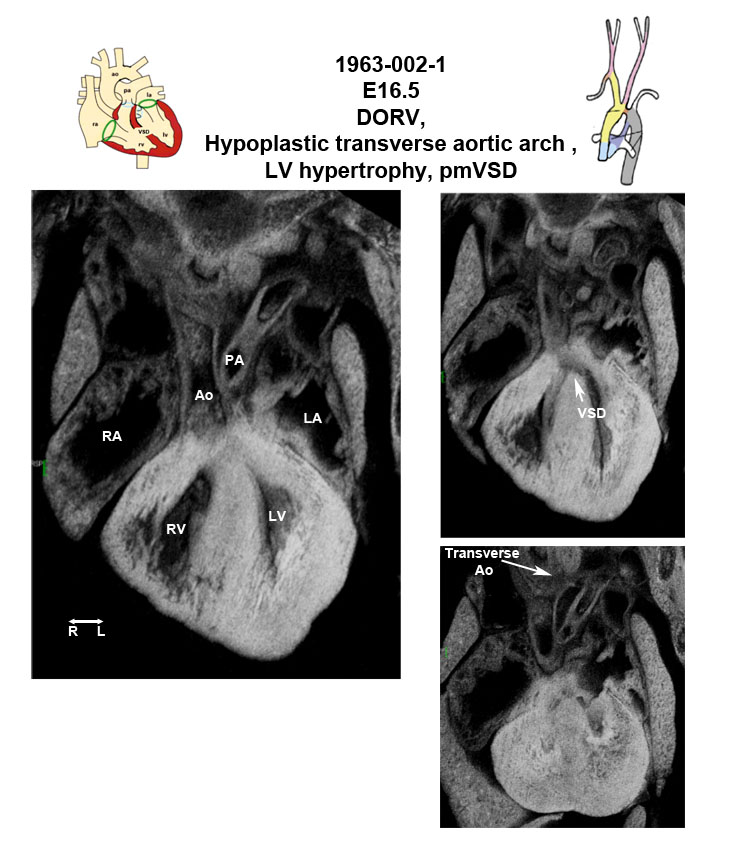

Caption EFIC summary

Copyright This image is from the Laboratory of Dr. Cecilia Lo, a member of the Cardiovascular Development Consortium (CvDC), Bench to Bassinet (B2B) program of the National Heart Lung and Blood Institute (NHLBI), and is displayed with the permission of the authors. J:175213

b2b1963Clo Mutant line 1963; Bench to Bassinet Program (B2B/CVDC), mutation 1963 Cecilia Lo

b2b1963Clo/b2b1963Clo C57BL/6J-b2b1963Clo